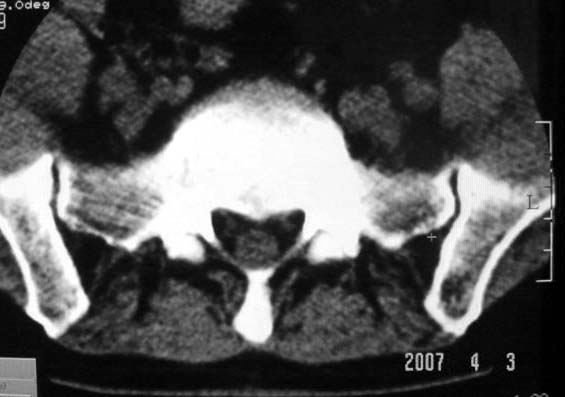

行腰椎间盘检查时,发现左侧髂骨后缘一类圆形低密度影,ct值约负43hu。

ct值-43hu,支持骨髓窦。骨髓窦是指松质骨内先天性骨小梁发于稀少,各组骨小梁之间的骨小梁少或缺失,形成一空腔,内含有骨髓,称为骨髓窦,为正常解剖变异。以跟骨多见,其次见于股骨颈、股骨远端及髋臼上缘等处。

既然是负值,那么考虑骨纤维结构不良、骨囊肿就不太合适了。由战友考虑骨髓窦,个人认为觉得也不妥。理由很简单,骨髓窦是一种骨骨松质内小梁发育稀少或缺失形成的空腔,因而张力较小,形态可以不规则。而本例病变形态规则呈圆形,且边缘轻度硬化,这些度不符合骨髓窦的特征。所以本例应该考虑骨内脂肪瘤